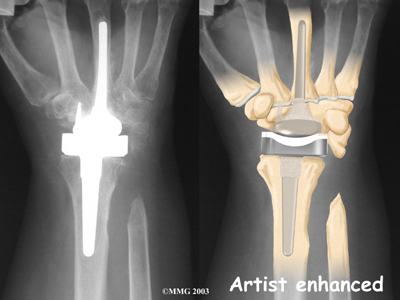

Modern artificial wrist joints are made of metal and plastic. The part that fits against the end of the radius bone of the forearm is called the radial component. It is made up of two pieces. A flat metal piece is placed on the front part of the radius. It has a stem that attaches down into the canal of the bone. A plastic cup fits onto the metal piece, forming a socket for the artificial wrist joint.

The part that replaces the small wrist bones is called the distal component. This piece is made completely of metal. It is globe shaped to fit into the plastic socket on the end of the radius. The metal distal component is attached by two metal stems that fit into the hollow bone marrow cavities of the carpal and metacarpal bones of the hand.

The plastic used in artificial joints is tough and slick. It allows the two pieces of the new joint to glide easily against each other as you move your wrist. The ball and socket allow movement of the wrist in all directions.

from the wrist. The end of the radius is also shaped to fit the prosthesis.

Replacement Joint

Cemented into Place